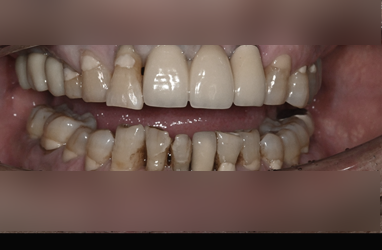

특히 틀니를 오래 사용했거나 심한 풍치(치주염)가 있었다면 뼈의 두께는 종잇장처럼 얇아지기도 합니다.

이 상태에서 무리하게 임플란트를 심으면 기둥이 잇몸 밖으로 비치거나, 금방 흔들려 빠질 위험이 큽니다.

마치 모래 위에 집을 짓는 것과 같기 때문입니다.